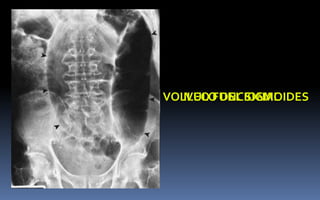

ILEO FUNCIONALVOLVULO DEL SIGMOIDES